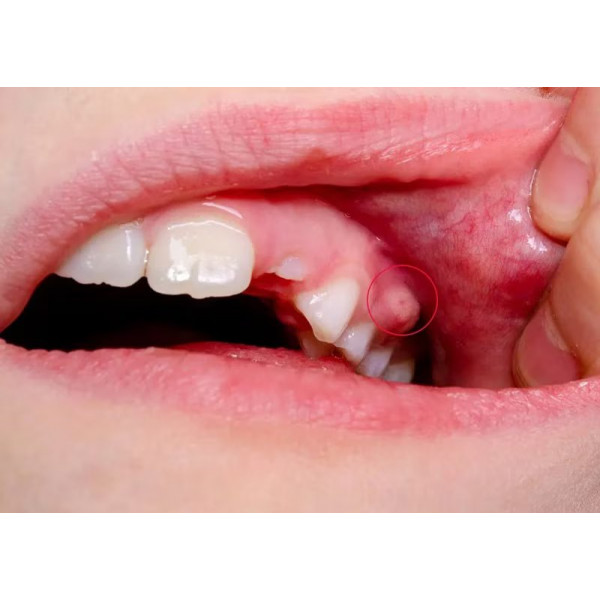

Một điểm đặc trưng của áp xe nha chu là mủ bị “kẹt” trong túi nha chu, không thoát ra ngoài. Áp lực nội mô tăng lên làm người bệnh đau dữ dội, cảm giác như răng bị đội lên hoặc cộm khi cắn. Đây là giai đoạn cấp tính cần xử trí nhanh vì mủ càng tích tụ, mô quanh răng càng bị phá hủy. Do đó, điều trị áp xe quanh răng cấp không thể trì hoãn.

Điểm quan trọng trong lâm sàng là nhận diện đúng áp xe để điều trị sớm. Áp xe quanh răng cấp thường gây đau dữ dội, sưng khu trú vùng nướu, có thể xuất hiện mủ hoặc hơi thở hôi. Răng đau khi gõ hoặc khi cắn, đôi khi có cảm giác răng “dài ra” do mô quanh răng phù nề. Đây là khác biệt so với đau răng do nhạy cảm đơn thuần.

Bước quan trọng nhất trong điều trị áp xe cấp là dẫn lưu mủ áp xe. Khi mủ được thoát ra, áp lực trong mô giảm nhanh, người bệnh sẽ thấy giảm đau rõ rệt. Dẫn lưu có thể thực hiện qua túi nha chu hoặc rạch dẫn lưu tùy mức độ sưng. Đây là bước mang tính “giải áp” và là nền tảng để các phương pháp khác phát huy hiệu quả.